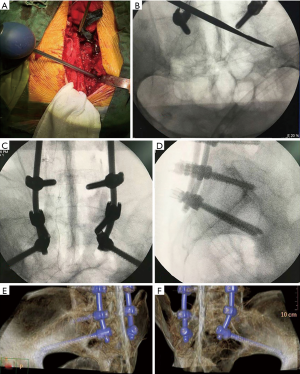

The optimal entry point of S2AI screw is located approximately 1 mm inferior and 1 mm lateral to the S1 dorsal foramen (11) (Figure 2), which is more medial and lower profile than iliac screw fixation. After determining the screw entry point, a drill or probe is used to fashion the screw trajectory (Figure 3), which can vary among individuals. Pre-operative screw trajectory measurements and intra-operative imaging may help optimize screw trajectory.

In 2015, Park et al. (18) reported the free hand S2AI insertion technique on cadaveric specimen. The midpoint between the S1 and S2 foramen and 2 mm medial to the lateral sacral crest was chosen as the entry point. After insertion of eight S2AI screws, visual and C-arm evaluation of the screw trajectory demonstrated accurate placement of all screws, with no violation of the sciatic notch, acetabulum, or pelvic cavity. The authors suggested that the free hand technique could reduce radiation exposure and surgical time.

S2AI screws can also be inserted percutaneously. O’Brien et al. (14) performed percutaneous S2AI fixation on eight cadaveric spines, with visualization of the first dorsal foramen through standard anteroposterior and inlet radiographs, avoiding visceral or neurovascular structure injury. Martin et al. (30) also performed percutaneous S2AI screw fixation on two patients (a 69-year-old female with follicular thyroid carcinoma metastatic to the sacrum and a 55-year-old male with a sacral fracture), reporting minimal blood loss without intraoperative complications and immediate achievement of stability. El Dafrawy and Kebaish (31) reported on a 65-year-old woman who had an iliac stress fracture that progressed to nonunion. The authors performed the percutaneous S2AI screw fixation technique on her, with symptom relief reported at 2 months and radiographic union at 6 months. Funao et al. (32) additionally reported that the use of percutaneous of S2AI screw fixation was effective in the treatment of two cases of spondylodiscitis (one at L4-5, another at L5-S1). All these studies support that percutaneous S2AI screw fixation is a feasible and safe technique, with the added benefit of limited soft tissue damage.